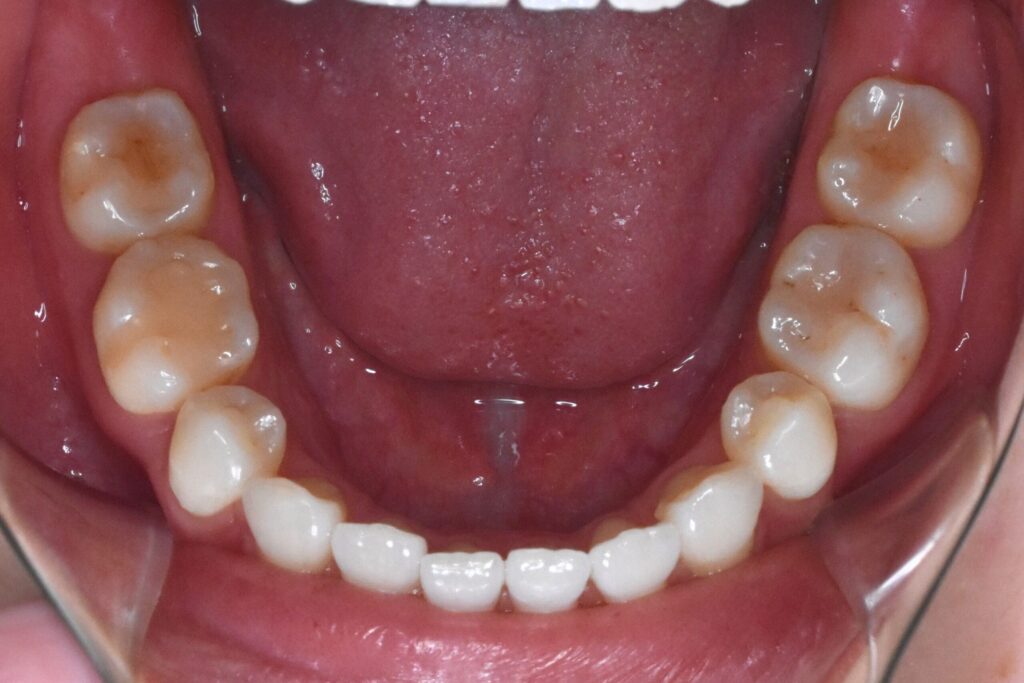

After